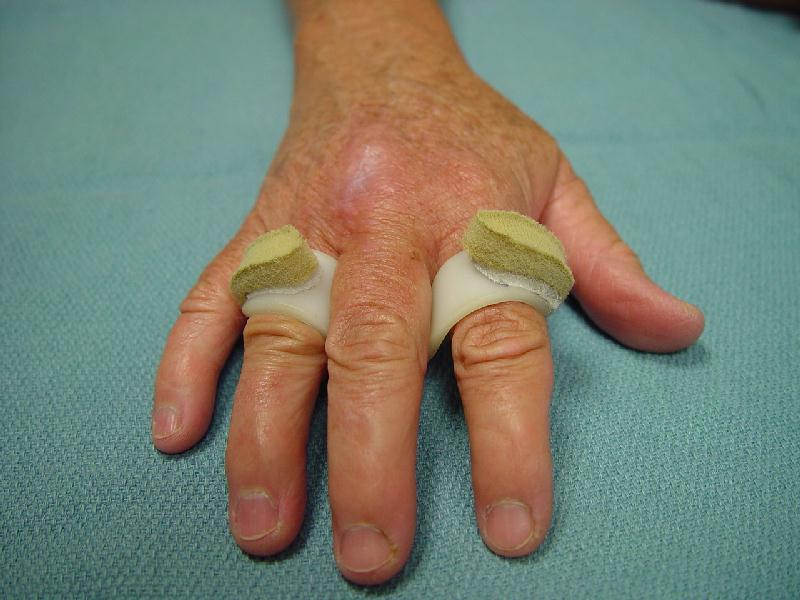

Cat bite injury, 2 days old, extensor tendon and metacarpophalangeal joint involvement, treated with radical excisional debridement and sealed continuous irrigation/suction. Extensor lag treated with "hammock" splint.